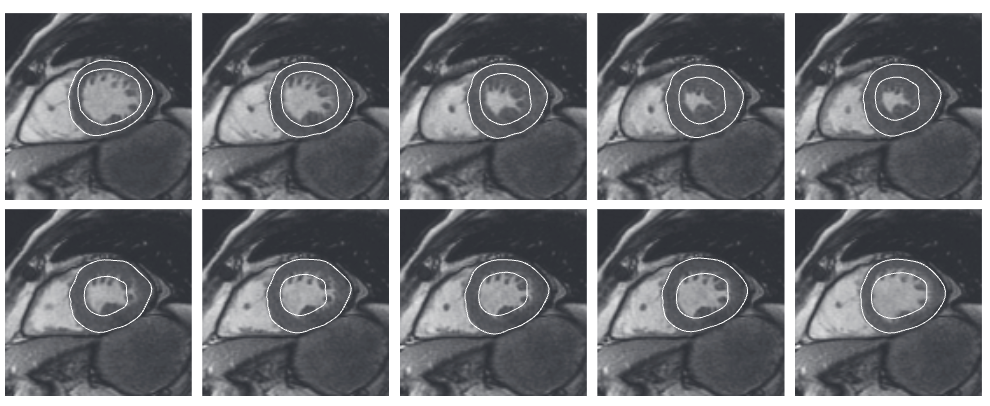

2014

1. Computer Vision

cardiac_tracking.png

Modeling and Estimation of Shape Deformation for Topology-Preserving Object Tracking

Valentina Staneva, and Laurent Younes

SIAM Journal on Imaging Sciences, Jul 2014